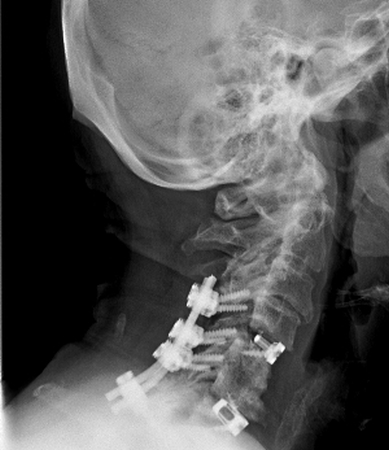

July 29th 8 Stainless Bolts, 2 Titanium Rods & 2 Implants